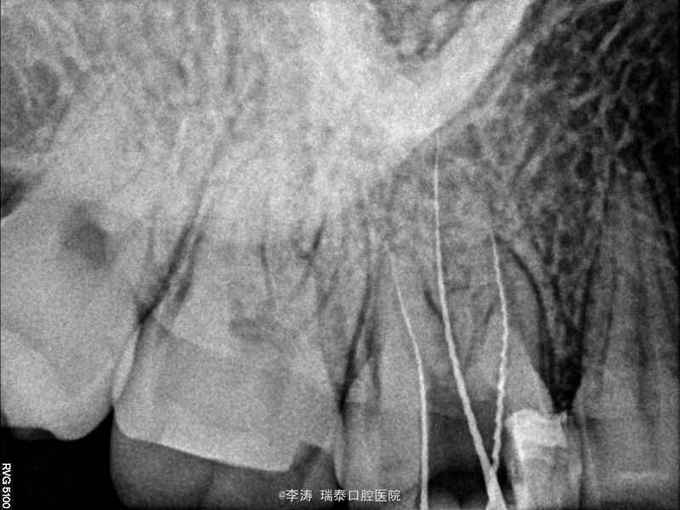

16牙合面大面积充填物,x线片根充不完善,根尖未见明显暗影

行16牙根管再治疗,嵌体修复

不知道大家有没有用TF,经常会觉得TF预备后的牙按它的锥度,牙胶尖老是下不去,但用k3或者protaper预备的根管确能按照针的锥度选择牙胶,是TF本身的问题吗?还是没有掌握预备方法?